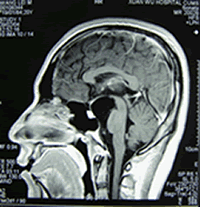

小腦蛛網膜囊腫 MRIAC 1831年,Bright首先描述AC。認為AC是位於兩層蛛網膜之間的內含清亮液體的囊腫。1958年,Starkman等對屍檢標本進行了系統正規的病理學研究,證實了127年前Bright對AC的論述。20年後,Rengachary等發表了有關AC的光鏡和電鏡照片,進一步證實了Bright的理論。該照片顯示,AC周圍的蛛網膜分為兩層,且囊腫內不含蛛網膜小梁。表明囊腫起自蛛網膜內,而並非起自蛛網膜下腔。囊腫包膜含有增殖的蛛網膜細胞和較厚的膠原層。囊腫周圍的腦組織通常結構正常,但也有部分病例伴膠質細胞增生。AC擴張的機制仍然存在爭論。囊腫壁自身可能分泌液體並使之擴張;腦脊液可能通過球瓣或裂隙瓣機制進入囊腫內並存留其中,使囊腫不斷增大;也可能囊腫與蛛網膜下腔自由交通,因腦脊液的搏動而使囊腫體積增大。

四疊體蛛網膜囊腫MRI表現一、組織學分型:

蛛網膜囊腫MRI表現CT 及 MRI 是蛛網膜囊腫最佳的診斷方法, 不但可以明確蛛網膜囊腫的部位、體積以及與周圍結構的關係,還能做出定性診斷。X線顯示蛛網膜囊腫鄰近骨質變薄、隆起或內板呈腦回壓跡樣凹陷等非特異性表現可作為輔助診斷。

2、MRI 檢查蛛網膜囊腫的特點為 T1 加權圖像示低信號,T2 加權像示高信號,與腦脊液信號相同。MRI 檢查可以了解病變與腦實質、腦池的關係,建立三維圖像,制定手術方案。鞘內注射造影對鑑別蛛網膜囊腫與其它囊性病變或腦池畸形有重要意義。用泛影葡胺造影, 蛛網膜囊腫被造影劑襯托出一圓形充盈缺損。MR 相位對比電影法可以有效了解腦脊液流通動力學,可鑑別蛛網膜囊腫和蛛網膜下腔擴張,也可了解囊腫與蛛網膜下腔交通情況,較鞘內造影檢查具有無創、準確性高的優點。